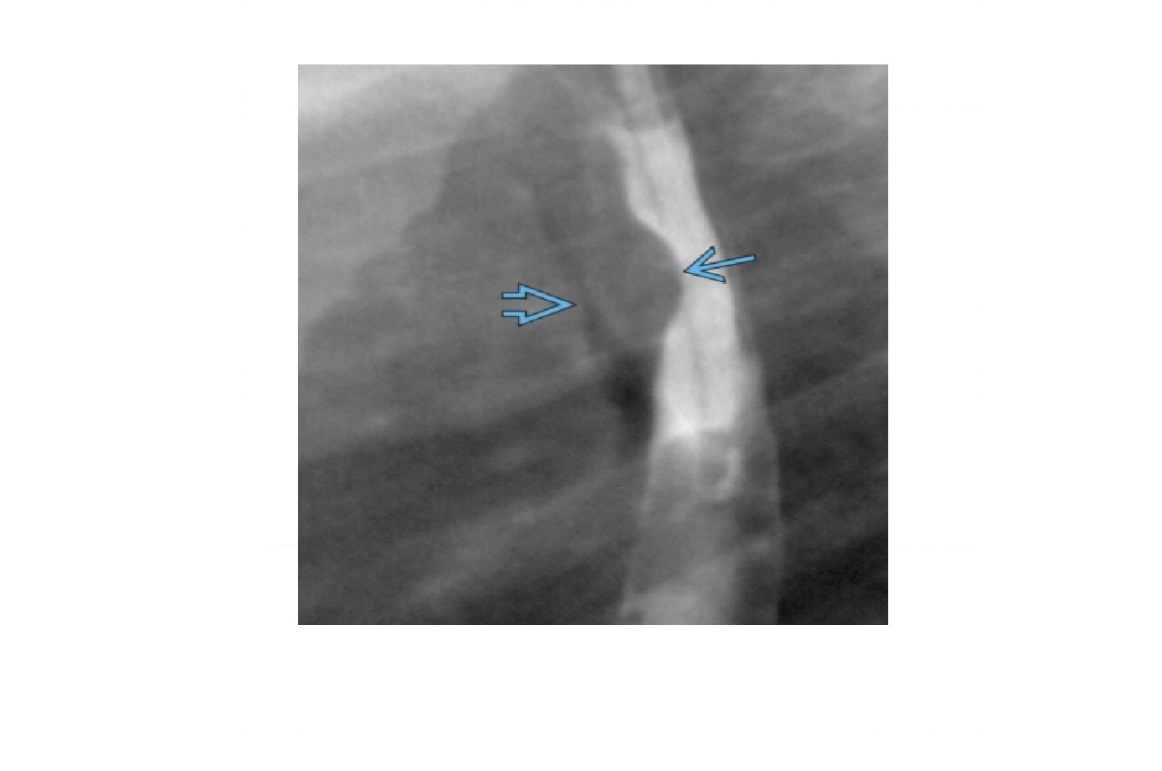

oesophageal scleroderma

-affects the Lower 2/3 (smooth muscle) with atony and peristalsis that begin caudally and moves cranially.

-Moderate dilatation of esophagus with fusiform stricture at lower end

Nb upper 1/3 to above aortic arch is normal (striated muscle)

Achalsia

- Grossly dilated whole oesophagus with smooth, beak-like tapering at lower end

Reflux Esophagitis (With Stricture)

-Longer tapered distal stricture

-Less luminal dilation

-Distinguished from scleroderma by normal peristalsis